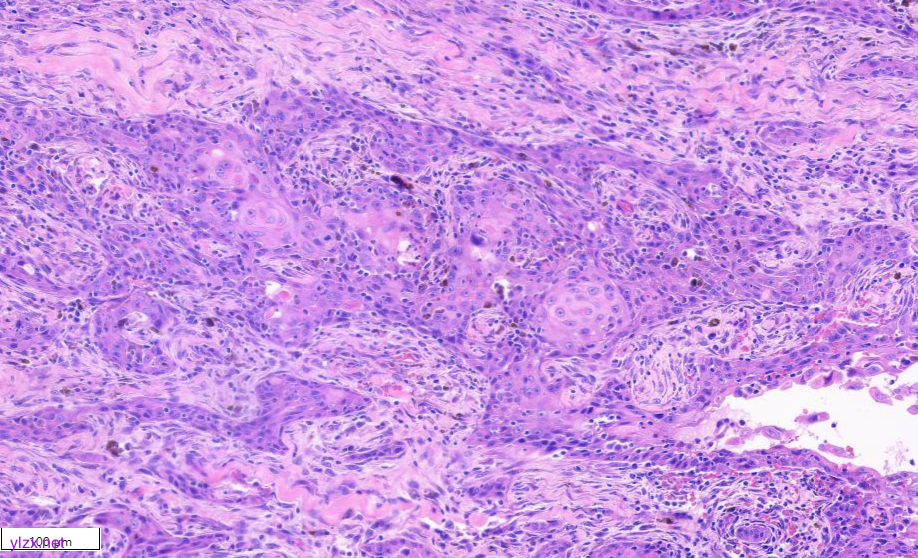

低倍镜下甲状腺乳头状癌区域与间变性癌鳞状细胞样亚型区域分界清,(图1)。低倍镜下,可见甲状腺乳头状癌呈乳头状、片状、索状分布,间质硬化(图2)。20倍镜,肿瘤细胞排列呈“铁轨”样,细胞立方形,细胞质丰富,淡嗜酸,细胞核圆,大小一致,染色质粗,核位于基底,可见小核仁,核内假包含体(图3)。鳞癌样区域(HEx10)肿瘤细胞呈多边形,梭形、上皮样,胞浆嗜酸,可见不全角化,肿瘤细胞间见脂褐素,肿瘤细胞侵袭性强,浸润至周围脂肪组织(图4、图5)。

图4 显示鳞癌区域(HEx4)